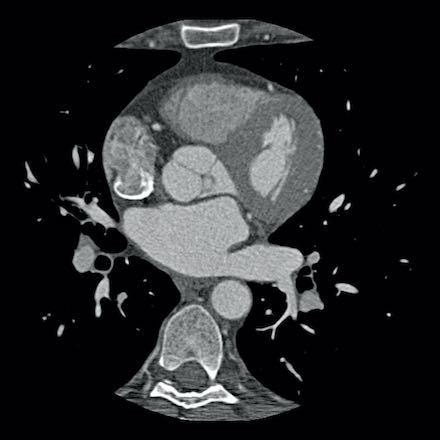

case 1 – CAD-RADS 2/P1

First, scroll through the scan.

Not all images are included. Some images without any abnormalities are skipped

from the series.

How would you describe the findings on the coronary CTA?

The findings are:

- Agatston score of

this patient was 14 (P1). Please, also note the calcification of the aortic valve. - Some partially

calcified and calcified plaques are present in the LAD with mild stenosis

(25-49%). - Calcified-plaque in

the LCX causing minimal stenosis (<25%). - Non-calcified

plaque in the distal RCA causing minimal stenosis (<25%). - This patient classifies

as CAD-RADS 2/P1, which means no further workup is needed.